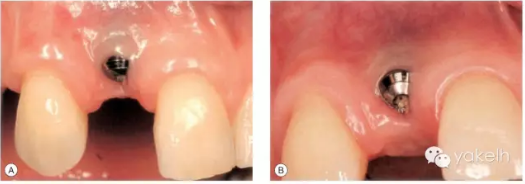

患者先天缺失側(cè)切牙,同時(shí)由于外傷UR1缺失。UR1種植修復(fù)。該種植冠大約有2mm 的牙齦退縮,與UL1相比,該修復(fù)冠較長(圖.8A)。這是由于種植體植入位置過深而導(dǎo)致的(圖.8B)。

圖.8 種植體植入過深,引起牙齦退縮以及修復(fù)冠過長。